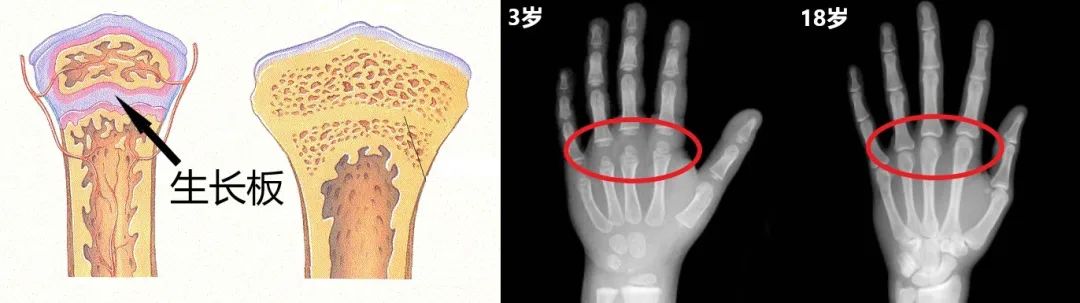

青春期身高猛增主要靠骨的长度增加,但不是整根骨均匀变长,新骨主要来自长骨末端的骨骺板(生长板),这里的软骨在激素和外力刺激下生长,增加骨的长度。 骨骺闭合之后,骨不能继续延长,也就达到了最终的成年身高 (这也是测骨龄的根据)。

左图-新骨从生长板长出来;右图-通过左手X线片观察骨骺以测定骨龄丨lyndarandy/Hand Bone Age